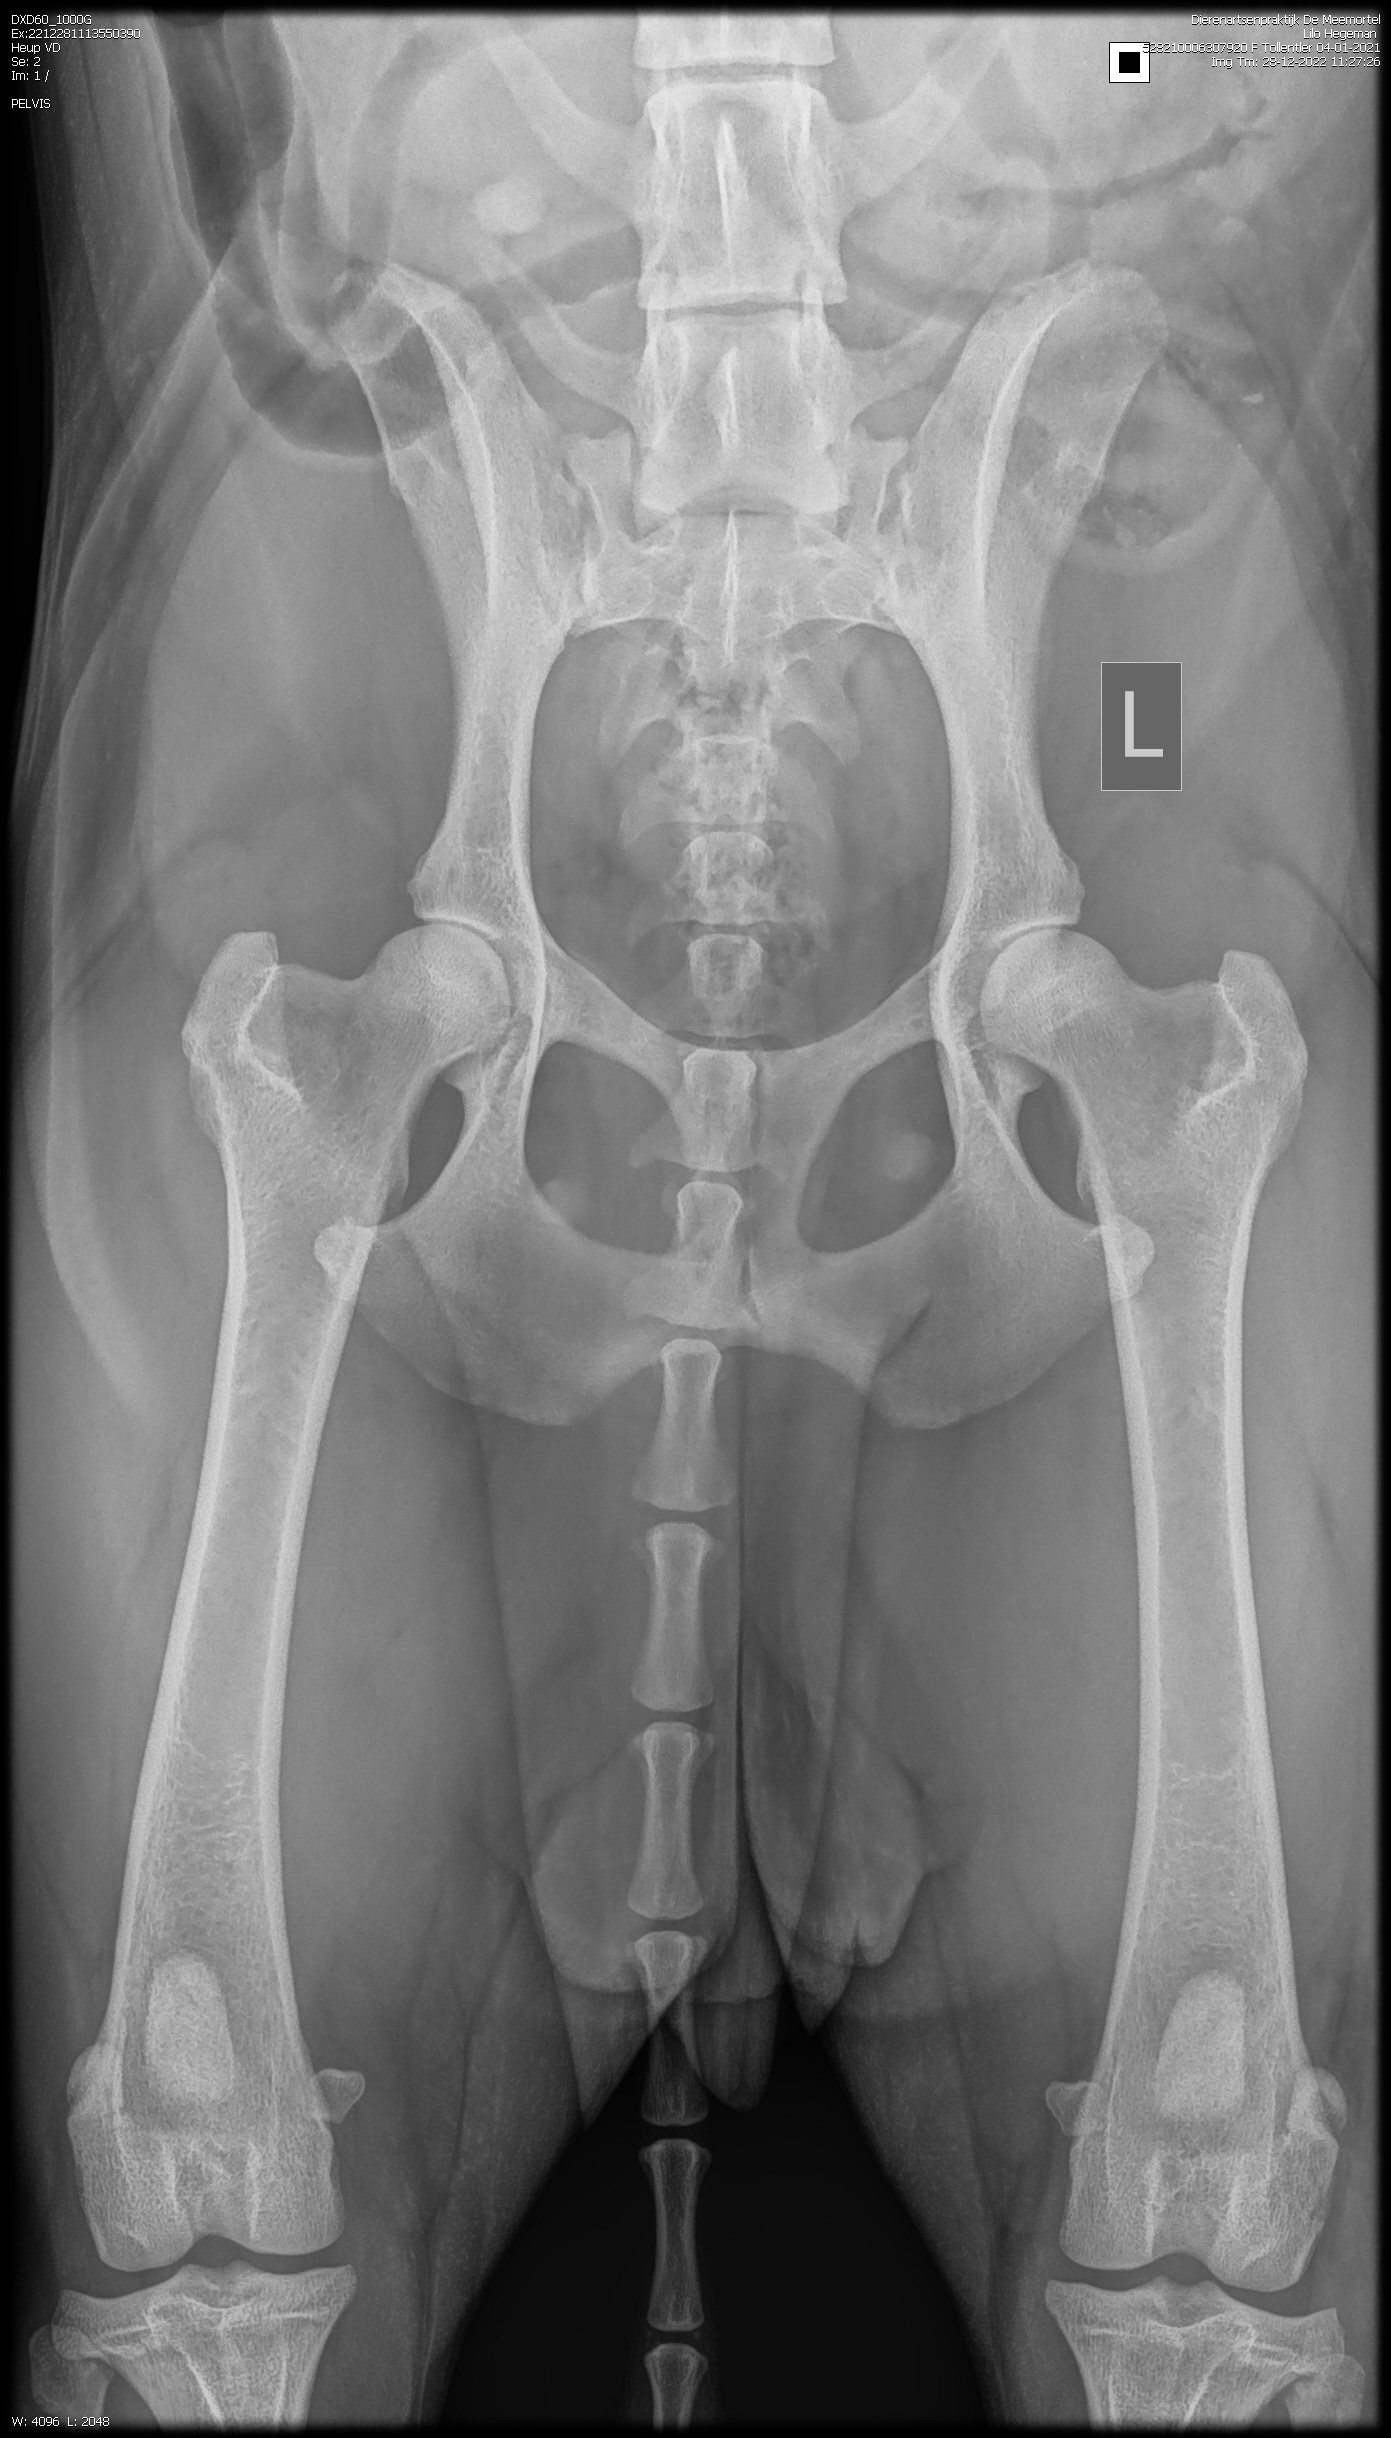

De heupen perfect zoals je kunt zien.

HD-A

Zo ook het overige. Zie onderstaand.